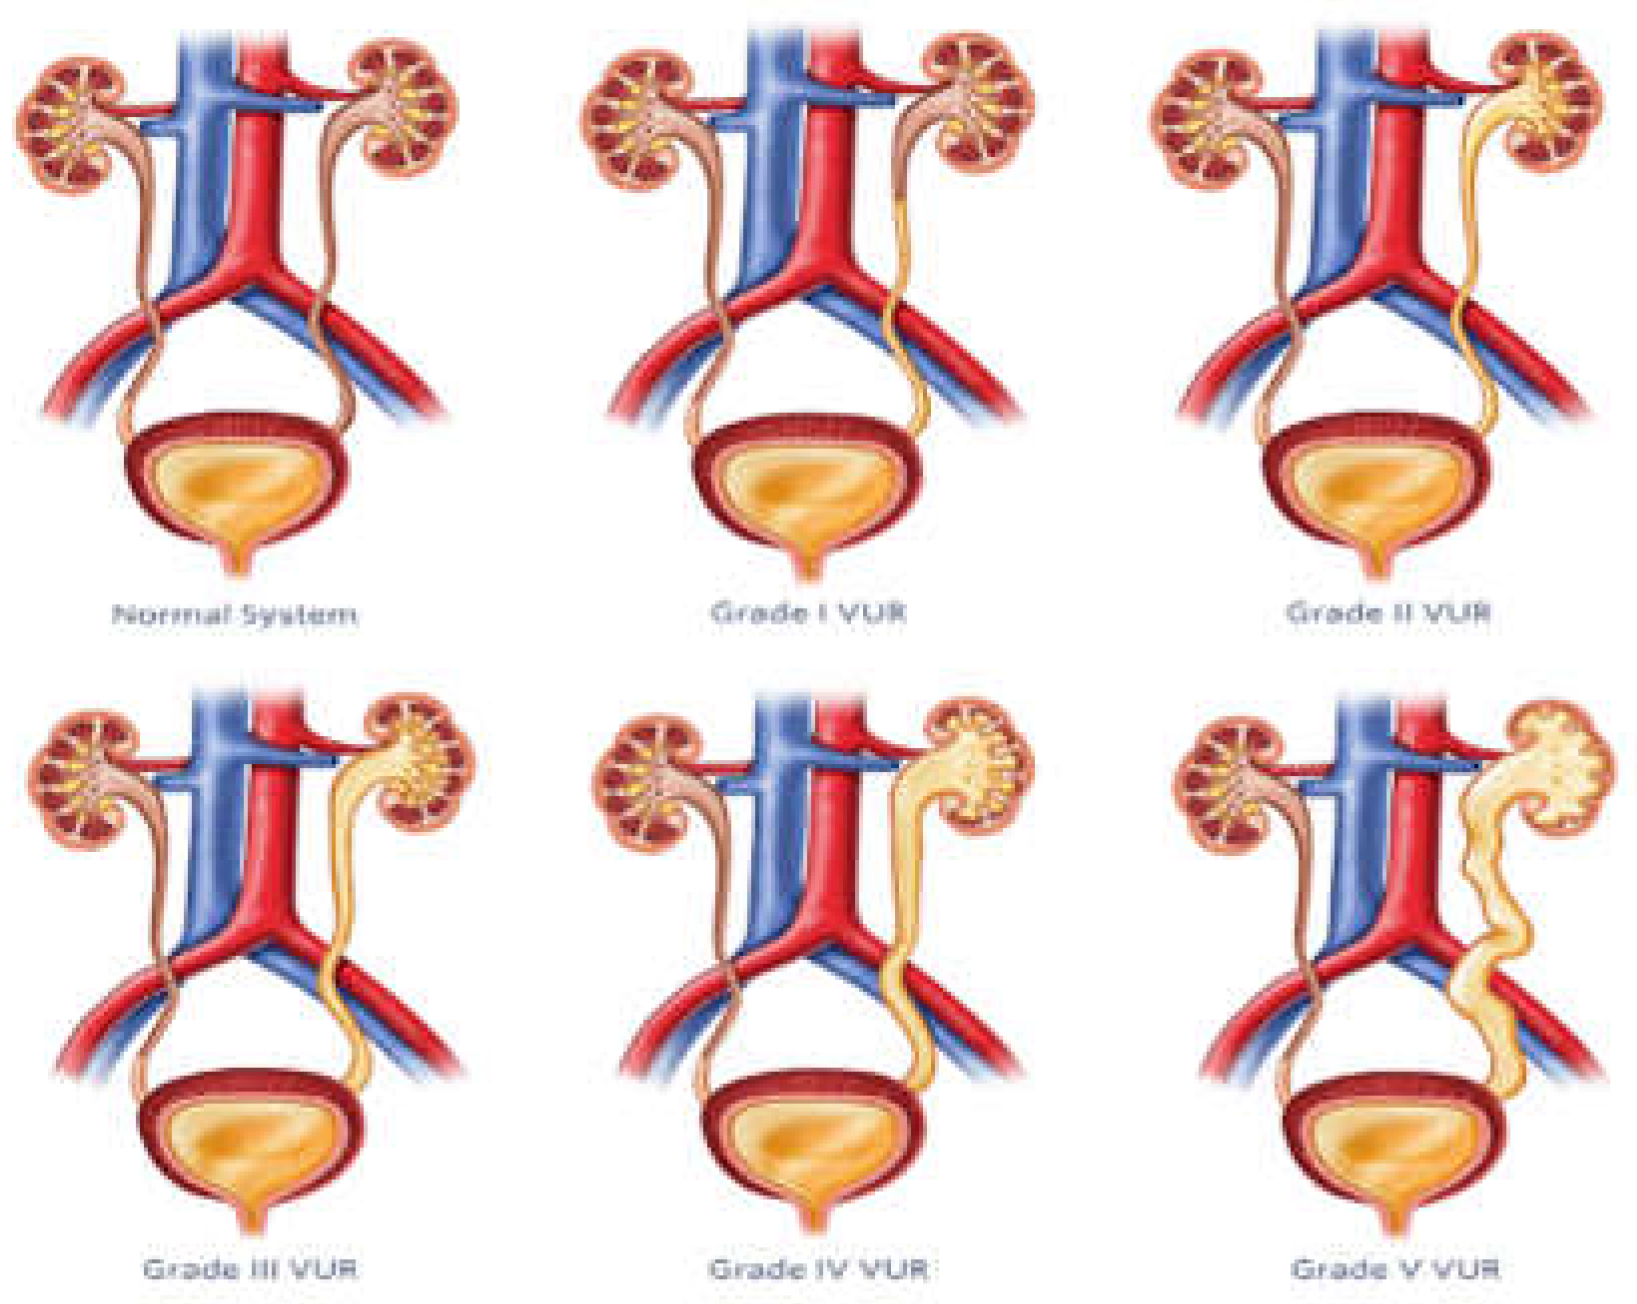

5. Vesicoureteral Reflux

VUR is a common pediatric urological condition characterized by retrograde flow of urine from the bladder into the ureters and kidneys. Failing to treat this condition can result in renal scarring and chronic kidney damage, highlighting the need for precise diagnosis and efficient management. Previously, diagnosis of VUR depended on invasive techniques such as VCUG and radionuclide cystography, which causes discomfort and poses significant risks for pediatric patients. Figure 8 illustrates the VUR grading system, which classifies this disorder into five groups based on the extent of urine backflow and dilation of urinary tract structures.

ML methods have also been used to improve the grading and diagnosis of VUR based on automated analysis of features collected from imaging studies [43,44]. This section aims to explore the diverse array of methods currently used for diagnosis and management of VUR in pediatric patients. Grade I: urine backflow into ureters but not kidney. Grade II: urine reaches the kidney but no renal pelvis dilation. Grade III: mild to moderate ureter and renal pelvis dilation. Grade IV: dilation of ureter, renal pelvis, and calyces. Grade V: severe dilation of ureters, renal pelvis, and calyces [45].